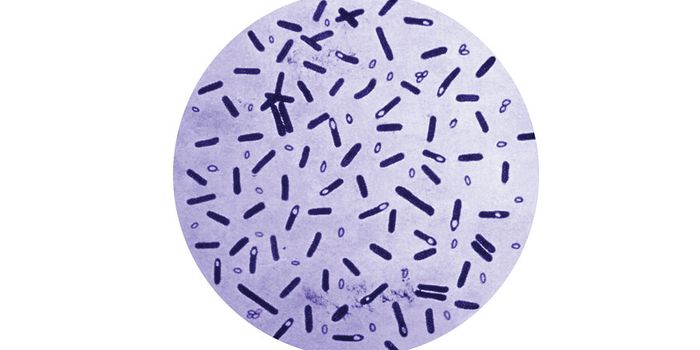

SEP 16, 2015MicrobiologyMethicillin-Resistant Staphylococcus Aureus (MRSA) is a dangerous bacterium that has become increasingly resistant to mu ...

NOV 30, 2016MicrobiologyLeprosy. We’ve all heard of it, but do you really know what causes it? What does the word make you think of ...

SEP 14, 2015MicrobiologyThis week Food Safety News named the 5 most dangerous foodborne pathogens. You may have heard of some of them due to med ...